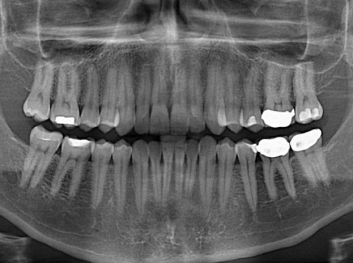

Adam Celiz,是來自諾丁漢大學的研究人員,他和同事開發(fā)的這種新型合成生物材料,能刺激干細胞在牙髓部的生長。與普通材料一樣,這種合成材料被填充到牙齒并用UV光硬化。

在體外測試中,材料刺激干細胞進入牙本質的增殖和分化速度,促進形成牙齒骨組織。研究人員認為,一旦材料在受損牙齒中應用,這些干細胞可以自動修復來自填充物上的損壞。在本質上,該生物材料將使牙齒自愈。

在未來,Adam Celiz說,可再生材料能制成各種填充物以便受損牙齒的自身治愈,降低補牙失敗率,甚至會消除大部分人對根管治療的需要。